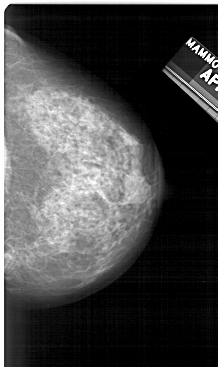

A_1279_1.LEFT_MLO

LEFT_MLO LINES 5176 PIXELS_PER_LINE 2731 BITS_PER_PIXEL 12 RESOLUTION 43.5 OVERLAY